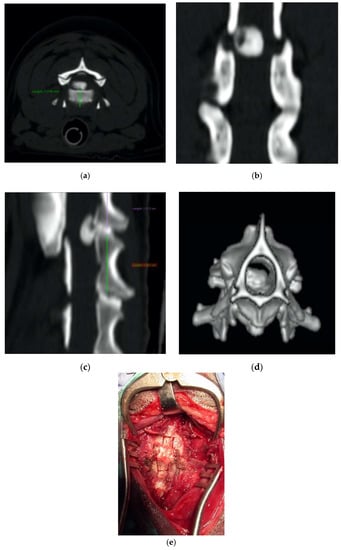

3.1.4. Case N° 4

Dachshund, female, seven years old, 8 kg, suffering from a progressive tetraplegia due to a cervical disk extrusion involving the C2-C3 space.

The dog underwent a ventral slot decompression by means of the piezoelectric bone scalpel with a curved long insert, which resulted in being very helpful, considering the depth of the surgical field compared to the dorsal approach (Figure 7). Two week later, the motor deficits significantly improved, and no signs of instability were documented.

Figure 7.

Axial (a), coronal (b), sagittal (c), and 3D (d) cervical CT scan showing a C2-C3 disk extrusion in a seven-year-old dachshund suffering from a progressive tetraplegia. Ventral slot decompression was obtained by means of long angled large saw tip (OT7, Osteotomy Tips Kit, Mectron Medical Technology, Genoa, Italy) (e).